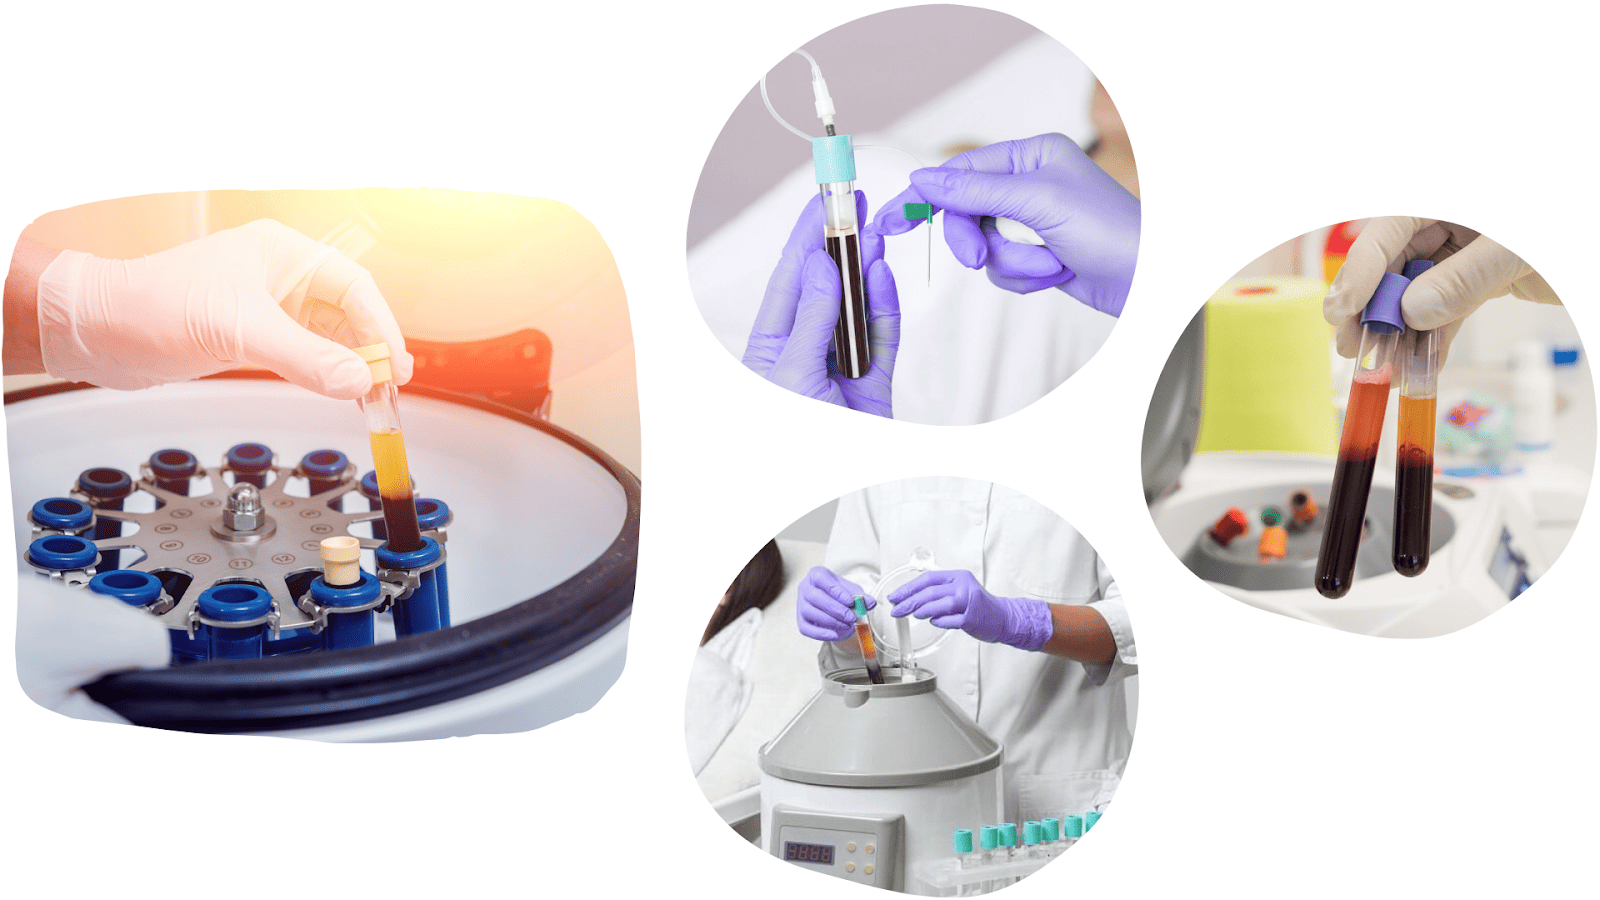

POMLAĐIVANJE LICA KRVNOM PLAZMOM

Pomlađivanje lica krvnom plazmom koristi prirodnu moć tijela za regeneraciju i pomlađivanje kože.

Postupak se izvodi tako da se iz male količine pacijentove krvi, nakon obrade pod visokom centrifugom, izdvoji plazma bogata trombocitima, koja se potom pomoću finih mikroiglica aplicira u kožu.

Riječ je o potpuno prirodnoj, sigurnoj i personaliziranoj metodi.

Trombociti oslobađaju brojne faktore rasta koji potiču obnovu tkiva, stvaranje fibroblasta, kolagena i hijaluronske kiseline.

Rezultat su obnovljeni volumen, smanjene bore, poboljšana elastičnost kože i ujednačen ten. Koža postaje hidratizirana, svježa i sjajna, a bore manje i pliće.

Prednost ovog tretmana je što ne sadrži sintetičke tvari, stoga nema nuspojava, alergijskih ili imunoloških reakcija.

Zahvat je jednostavan, bezbolan i potpuno siguran, a njime tretiramo lice, vrat i dekolte.

Pomlađivanje lica krvnom plazmom najbolji je i najprirodniji estetski anti age tretman lica koji si možete pružiti.